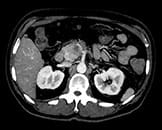

View an anatomical area using different spectral results.

Created by removing the iodine component from the image. Hounsfield Unit (HU) measurements from virtual non-contrast spectral results are comparable to true non-contrast scans for the majority of the organs, allowing VNC results to replace a true non-contrast scan.